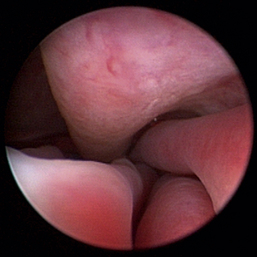

Nasopharyngeal Diseases

The hallmark symptom of nasopharyngeal disease is stertor. Discharge, sneezing, reverse sneezing, and hacking may be present variably. If the main complaint is noisy breathing and not productive sneezing with nasal discharge, the nasopharynx may be the site of primary disease. The most common primary problems in the nasopharynx in cats are inflammatory polyps and tumors.12,13 Cats with polyps are generally young and have a history of noisy breathing. Sneezing and mucopurulent nasal discharge may be present, but the chief complaint is stertor and increased respiratory effort. This is a problem that often requires otoscopic as well as rhinoscopic intervention. With the patient placed in dorsal recumbency, the soft palate is reflected rostrally with the use of a spay hook, and the polyp is removed via traction and avulsion (Figures 19-18 and 19-19). The eustachian tube orifices can generally be directly visualized and any remaining tissue removed, if present. Both ears should be carefully examined, and transtympanic bulla curettage should be performed to remove any middle ear proliferative tissue (see Chapter 20). In older cats with similar symptoms, a neoplasm in the nasopharynx is more likely, and rhinoscopy is often much more rewarding (Figure 19-20). Foreign bodies can become lodged in this area after vomiting or pharyngeal nasopharyngeal spasms induced by attempted swallowing of the foreign object. Nasal and nasopharyngeal stenosis after trauma, nasogastric reflux,14 and chronic rhinitis can occur in dogs and cats (Figures 19-21 through 19-23). Reflux can occur during general anesthesia and can be a helpful clue if postoperative symptoms arise and persist. Congenital choanal atresia and nasopharyngeal dysgenesis have also been reported in dogs.15,16 Nonspecific chronic inflammation of the nasopharynx causes a cobblestone appearance of the mucosa due to the formation of hyperplastic lymphoid follicles (Figures 19-24 and 19-25). Chronic inflammation may be the result of a lymphoplasmacytic rhinitis complex or sometimes may be secondary to otitis media and middle ear drainage of infected secretions via the eustachian tube. Otoscopy is recommended in any patient with nasopharyngitis of unknown origin. CT studies performed in a population of 45 cats with chronic sinonasal discharge revealed effusive bulla disease in 28% of symptomatic cats.17 Unfortunately, we are unable to differentiate primary and secondary pathology based on the concurrence of nasal and middle ear disease. Regardless of the knowledge of the primary cause, both inflammatory foci should be treated to achieve symptom relief.

Figure 19-20 Feline nasopharyngeal adenocarcinoma.

image